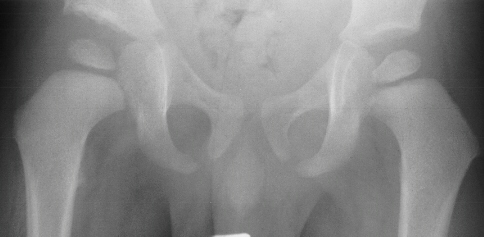

HISTORY: A 29 week old gestation male presented with bilateral knee dislocation, left hip subluxation, and right hip dislocation.

XRAYS: Reveal bilateral knee dislocations , and a left hip dislocation .

Hips were placed in traction for 2 weeks full time, and 6 weeks part-time( 12hr/day). The right hip failed traction: than had an open reduction and varus osteotomy at 1 year of age.

RESULT: ROM: R. knee 0-110 degrees, L. knee 0-120 degrees.; he started ambulating 18 months with a well reduced femoral head .